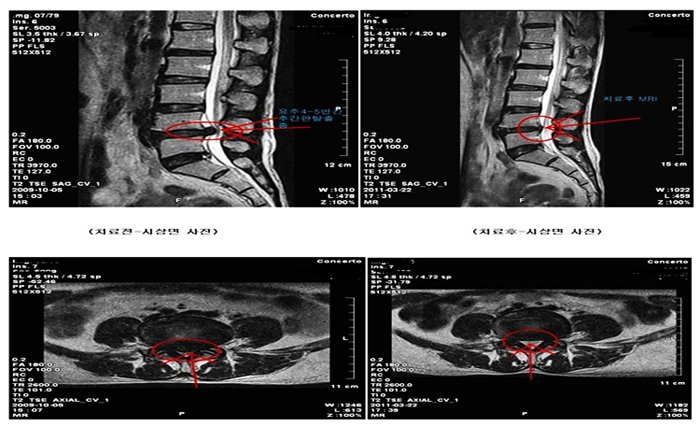

Pre and post treatment benefits can be documented using MRI scan. A six months post treatment MRI is recommended to document the progressive benefits of the treatment.